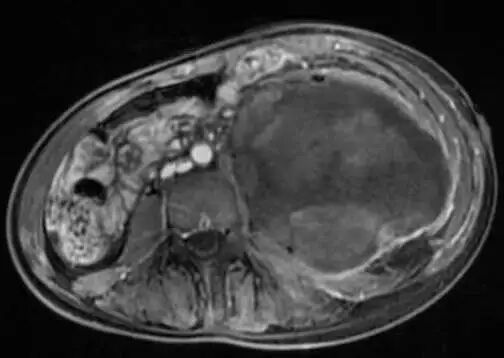

术前影像资料提示:患者左侧腹膜后存在一巨大恶性神经鞘瘤,最大径达20.1厘米。肿瘤已广泛侵犯周围结构,包括同侧髂骨、腰椎以及输尿管。